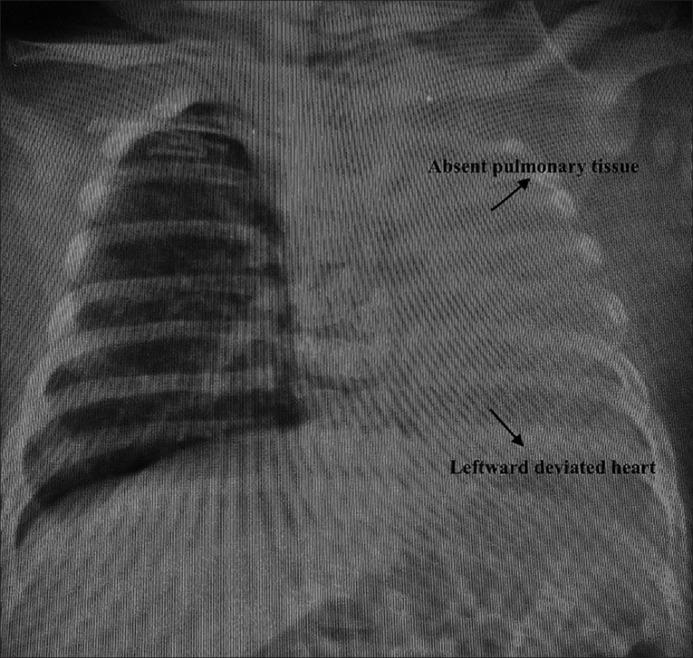

Glenn followed by Fontan are still the main two procedures for the treatment of patients with single ventricle. Some patients may be challenging due to unfavorable cardiopulmonary anatomy. In this report, we present Glenn shunt procedure in a patient with single pulmonary artery and congenitally agenetic lung.

格林手术继以Fontan手术仍然是治疗单心室患者的主要两种术式。一些患者可能因心肺解剖结构不佳而具有挑战性。在本报告中,我们介绍了一名患有单支肺动脉和先天性肺缺如患者的格林分流术。